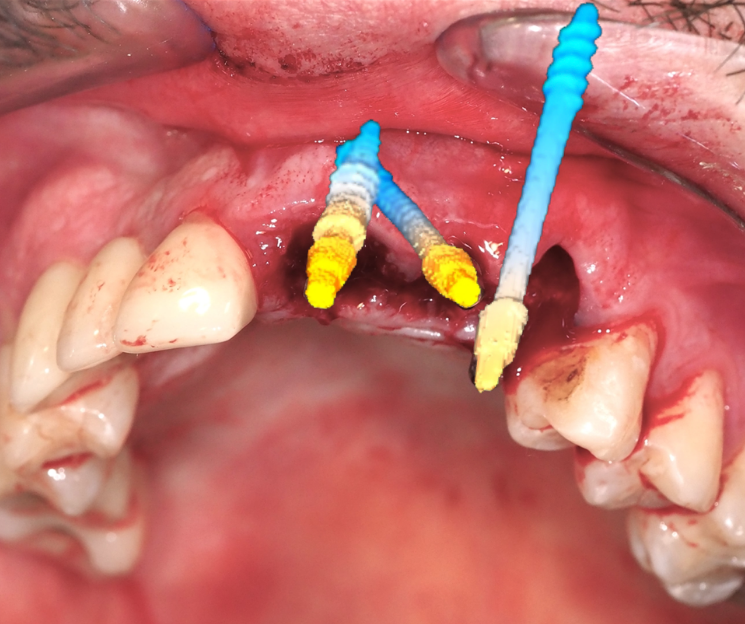

Extracción de piezas 21, 22 y 23 con infección activa

Paciente con infecciones de origen dental que comprometían severamente el hueso alveolar en la zona anterior superior. Se realizó la extracción de los dientes 21, 22 y 23, y se optó por una rehabilitación inmediata mediante implantes córticobasales.

Estrategia protésica e implantes utilizados:

- 1 implante córticobasal compresivo

- 2 implantes córticobasales rectos y finos

Esta combinación permitió anclar los implantes en hueso cortical, que mantiene su estabilidad incluso en presencia de procesos infecciosos en el hueso alveolar. El resultado: rehabilitación funcional y estética el mismo día de la cirugía.